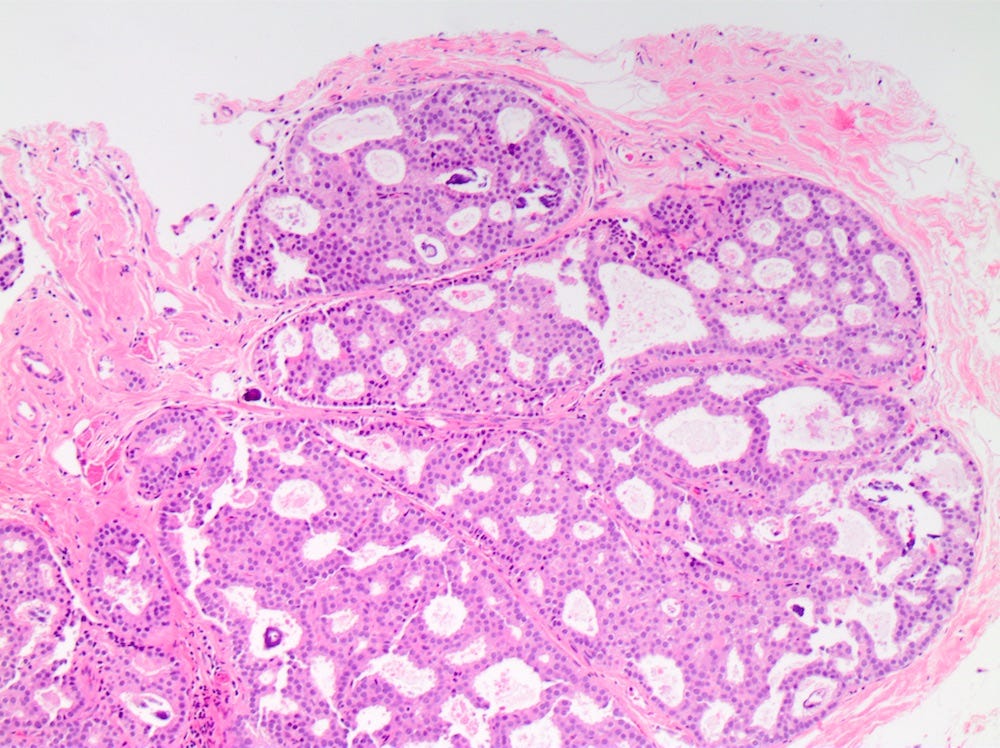

Ductal carcinoma in situ (DCIS) is a neoplastic proliferation of breast ductal epithelial cells within the ductal-lobular system with malignant microscopic features but without evidence of invasion through the epithelial basement membrane or myoepithelial cell layer into the surrounding stroma.

DCIS includes a heterogeneous group of lesions in terms of microscopic appearance, molecular alterations, biomarker expression profile and biologic potential for progression to invasive carcinoma. It is divided into low grade (less aggressive) DCIS and high grade DCIS. Normal breast tissue appears to transform to only one of these entities through two distinct molecular pathways (i.e. high grade DCIS does not typically arise from low grade DCIS). Low grade DCIS shows frequent chromosomal losses at 16q. High grade DCIS shows frequent losses at 8p and gains at 17q and has a similar molecular profile as invasive breast cancer.

DCIS - microscopic images